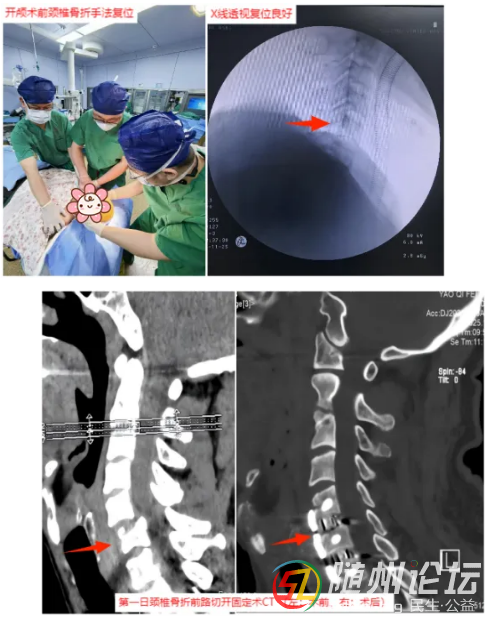

影像檢查顯示,患者顱內(nèi)出血位于左側(cè)額頂部上矢狀竇邊緣,隨時可能因出血加重或腦壓增高致命;同時頸椎骨折嚴(yán)重壓迫脊髓,如不及時處理,將面臨高位截癱風(fēng)險。神經(jīng)外科與脊柱外科專家經(jīng)過緊急會診,審慎評估,制定了周密的同期手術(shù)方案:ICU及手術(shù)室維持生命體征穩(wěn)定,必須盡快清除顱內(nèi)血腫、降低顱壓,同時復(fù)位頸椎、解除對脊髓的壓迫。

隨即,搶救團隊爭分奪秒。脊柱外科團隊首先對頸椎進(jìn)行手法復(fù)位,為后續(xù)手術(shù)創(chuàng)造條件;隨后,神經(jīng)外科團隊立即進(jìn)行開顱手術(shù),精準(zhǔn)清除腦內(nèi)血腫,妥善處理出血點,并將碎裂的顱骨修復(fù)還原;鑒于頸椎骨折仍需穩(wěn)固內(nèi)固定以最大限度保護(hù)脊髓功能,緊接著,脊柱外科團隊再次手術(shù),對頸椎進(jìn)行內(nèi)固定,穩(wěn)定骨折部位,解除對脊髓的壓迫。整個救治過程環(huán)環(huán)相扣,緊張有序。